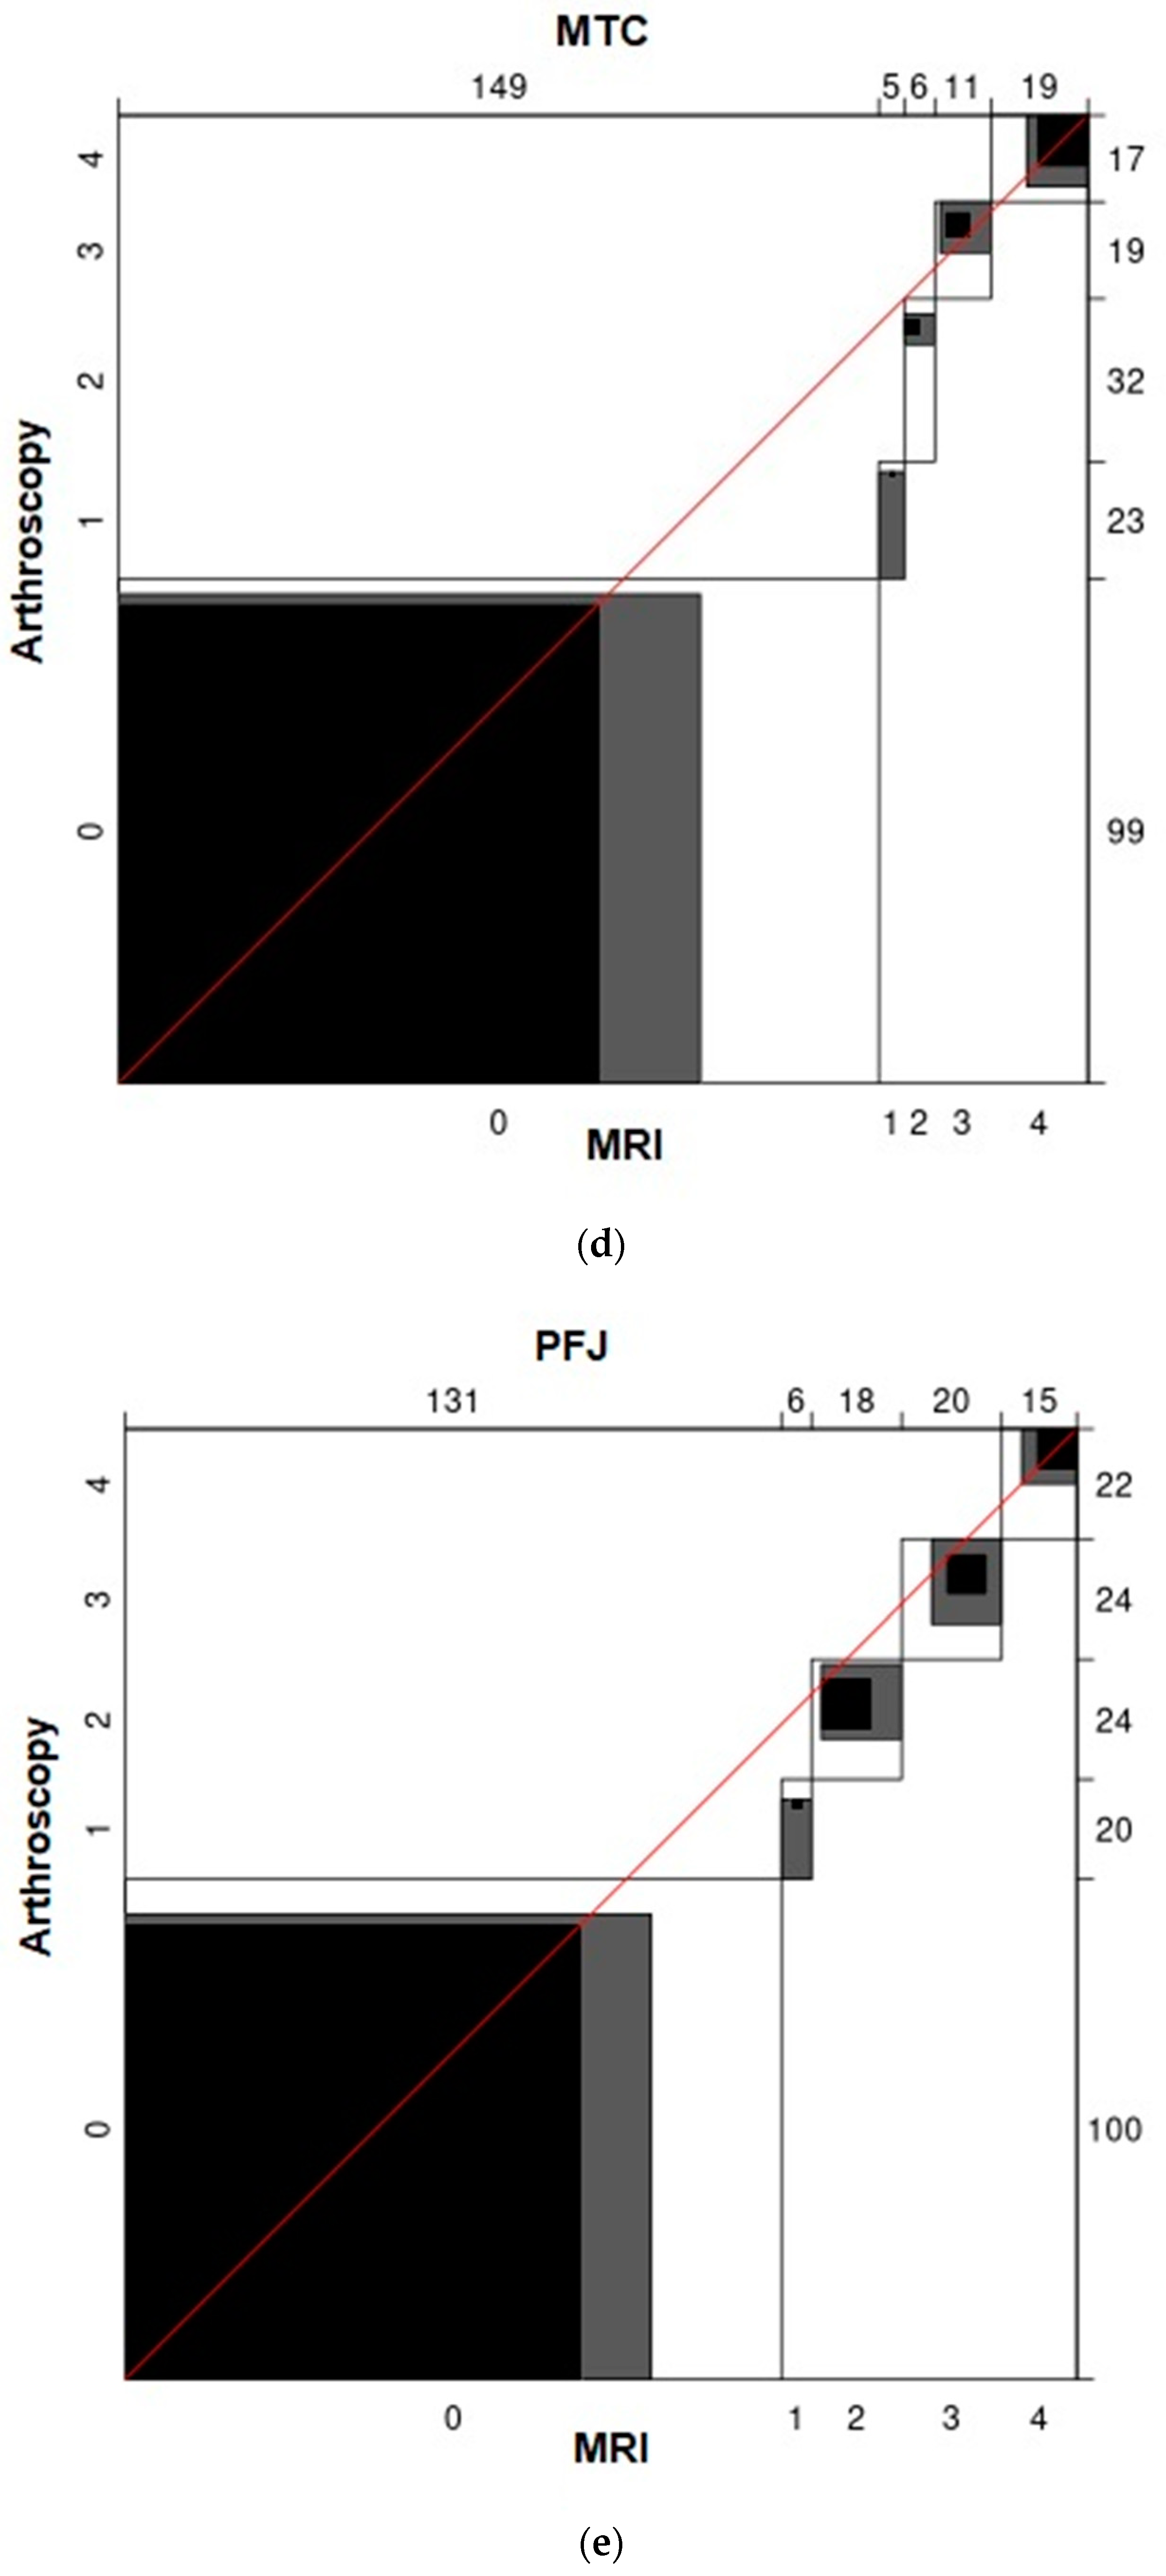

3. Results

| Location | Cartilage Status According to ICRS | Cartilage Lesions in Total | ||||

|---|---|---|---|---|---|---|

| 0 | 1 | 2 | 3 | 4 | ||

| MFC | 72 | 15 | 24 | 36 | 43 | 118 |

| LFC | 113 | 29 | 25 | 19 | 4 | 77 |

| MTC | 99 | 23 | 32 | 19 | 17 | 91 |

| LTC | 113 | 32 | 28 | 11 | 6 | 77 |

| PFJ | 100 | 20 | 24 | 24 | 22 | 90 |

| Total | 497 | 119 | 133 | 109 | 92 | 453 |

| Value | ASE | z | ||

|---|---|---|---|---|

| MFC | Unweighted | 0.39 | 0.046 | 8.387 |

| Weighted | 0.57 | 0.054 | 10.684 | |

| LFC | Unweighted | 0.13 | 0.042 | 3.015 |

| Weighted | 0.36 | 0.077 | 4.739 | |

| MTC | Unweighted | 0.29 | 0.047 | 6.094 |

| Weighted | 0.56 | 0.064 | 8.777 | |

| LTC | Unweighted | 0.10 | 0.041 | 2.473 |

| Weighted | 0.35 | 0.092 | 3.819 | |

| PFJ | Unweighted | 0.38 | 0.049 | 7.626 |

| Weighted | 0.50 | 0.069 | 7.335 |